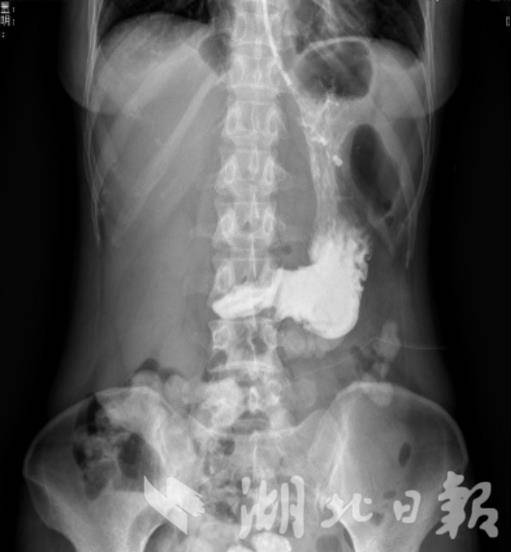

术前上消化道造影

“胃下垂合并胃排空延迟个体差异大,精准评估是诊疗关键。”闫瑞承主任介绍,黄女士入院后,团队为她安排胃超声造影等系列检查,确诊其胃小弯切迹已降至盆腔髂棘连线以下5厘米,胃排空速度仅为正常人的1/3。